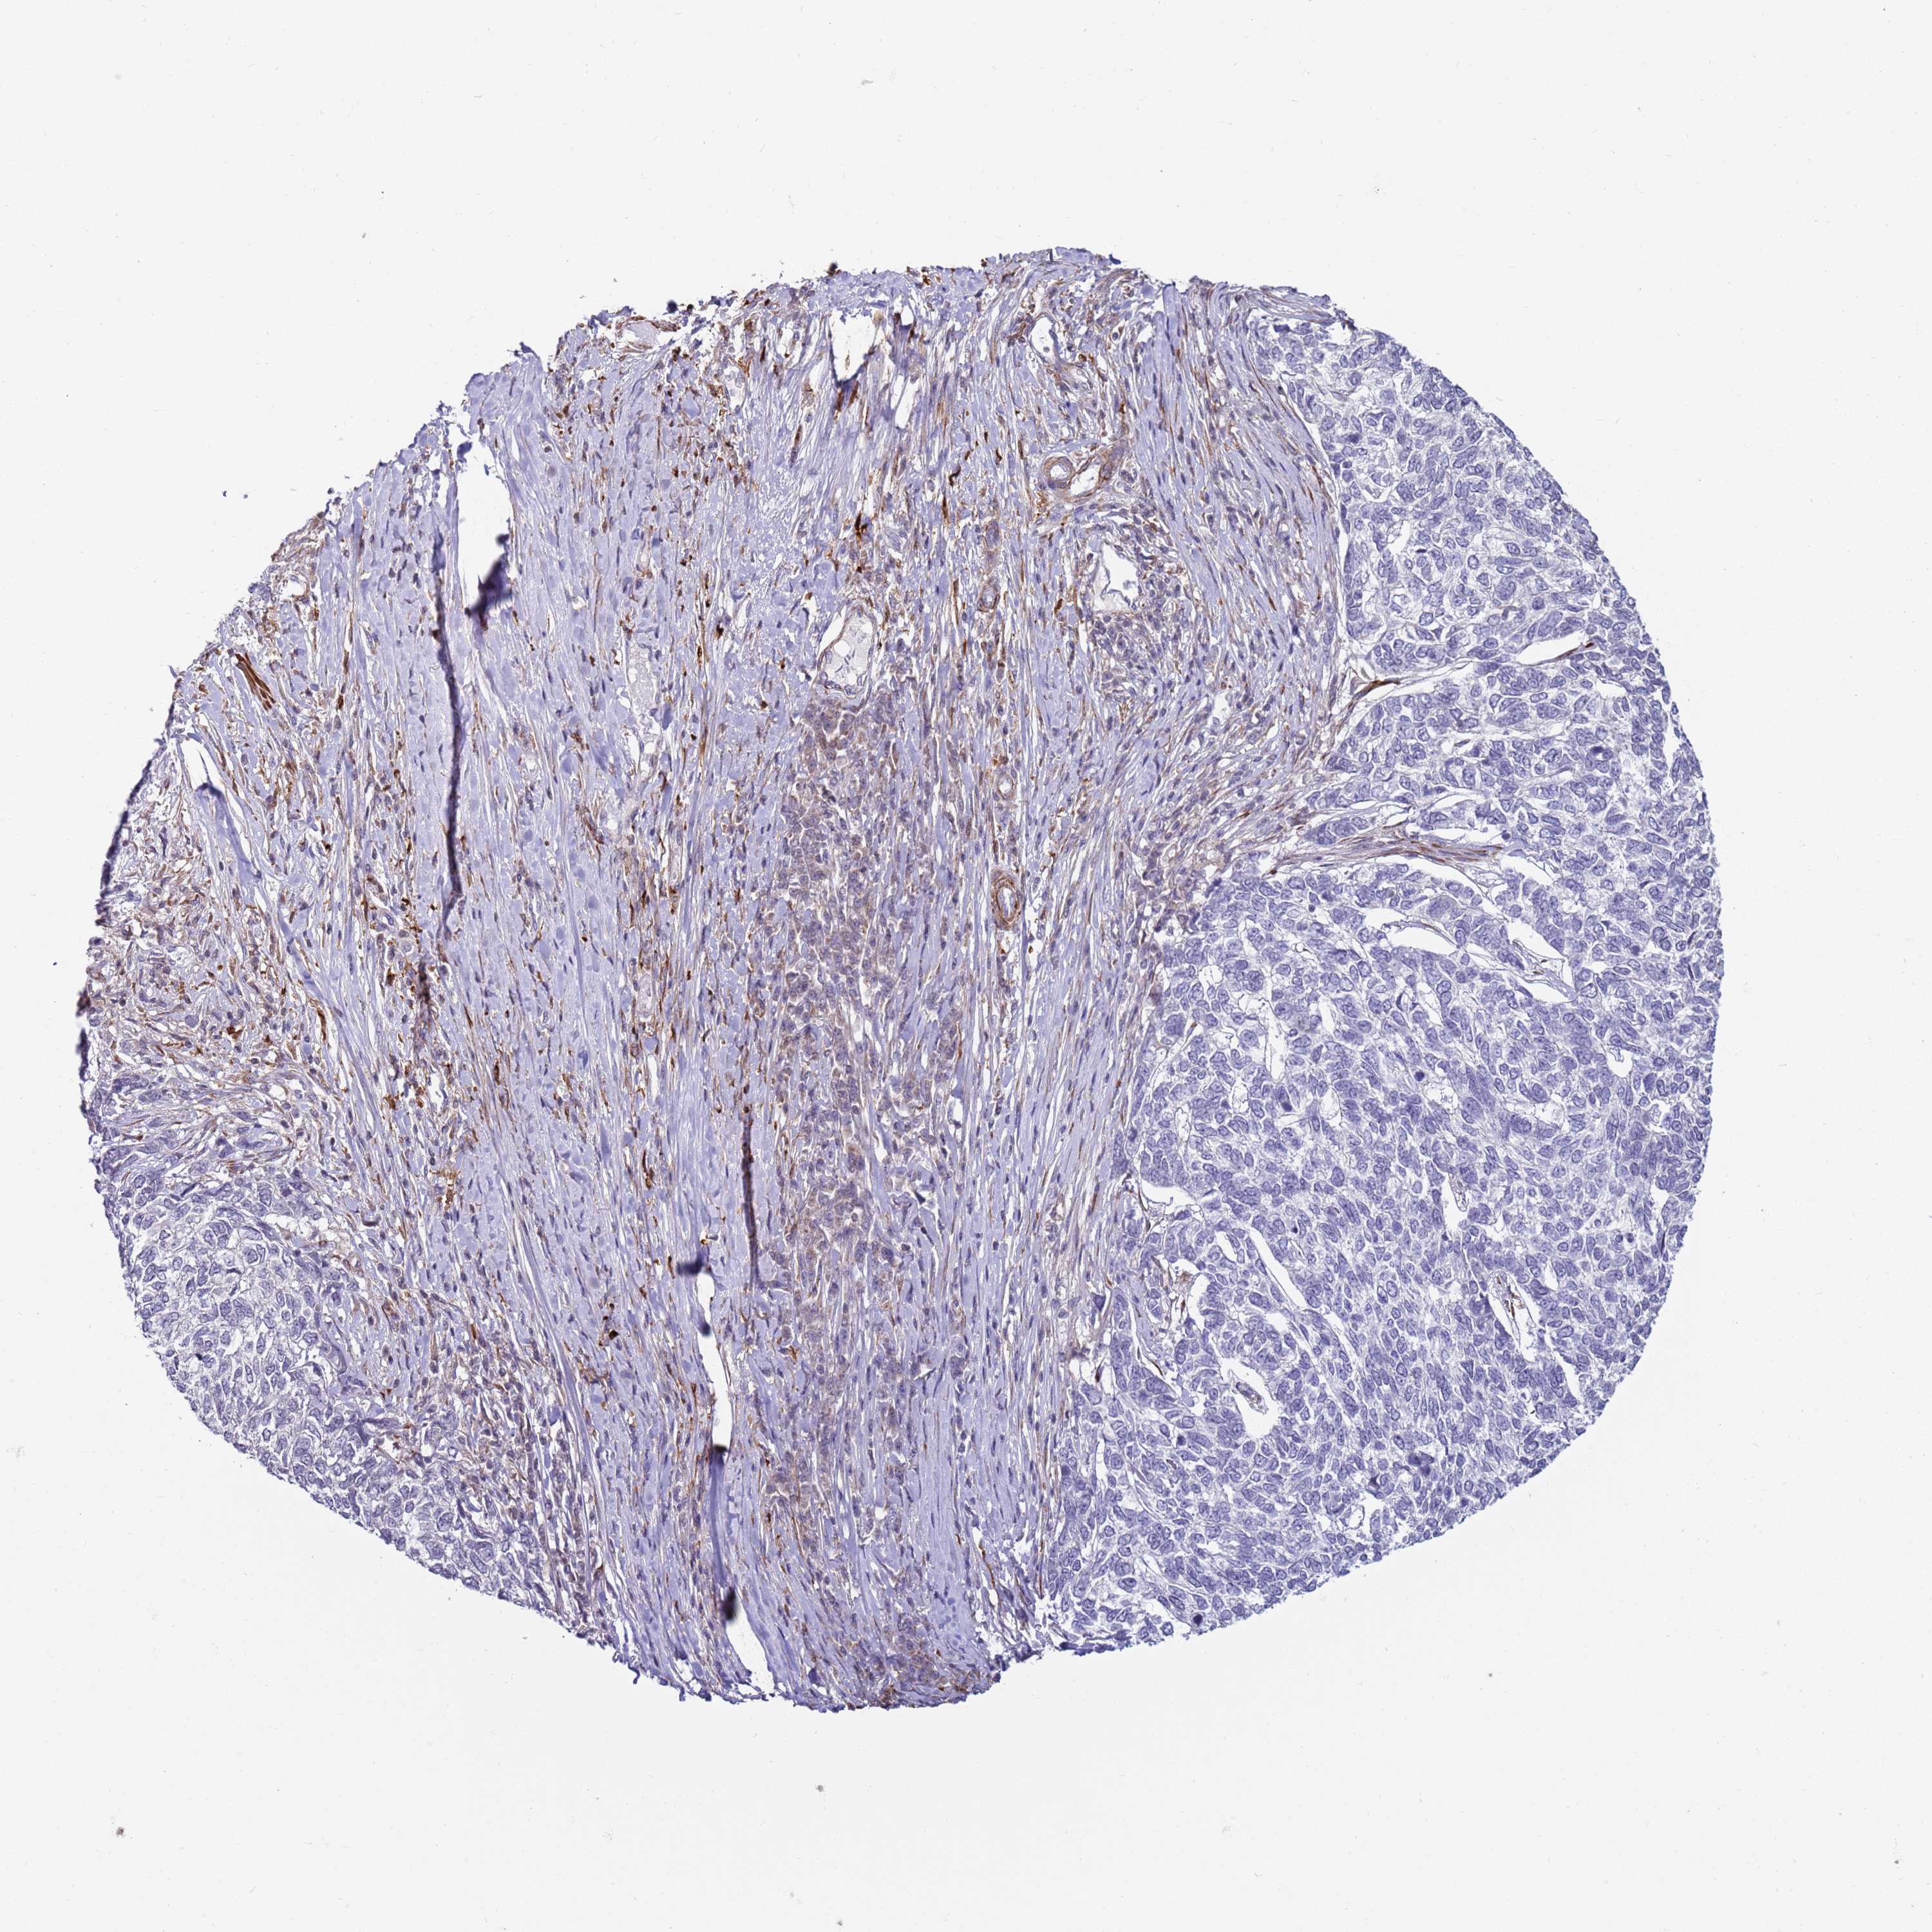

SKIN CANCER - Protein expressioni

A mouse-over function shows sample information and annotation data. Click on an image to view it in a full screen mode. Samples can be filtered based on level of antibody staining by selecting one or several of the following categories: high, medium, low and not detected. The assay and annotation is described here.

Antibody staining in the annotated cell types in the current human tissue is reported as not detected, low, medium, or high, based on conventional immunohistochemistry profiling in selected tissues. This score is based on the combination of the staining intensity and fraction of stained cells.

Each image is clickable and will lead to virtual microscopy that enables deeper exploration of all samples and also displays staining intensity scores, fraction scores and subcellular localization as well as patient and tissue information for each sample.

Antibody HPA046627

Basal cell carcinoma

Squamous cell carcinoma, NOS

Squamous cell carcinoma, metastatic, NOS